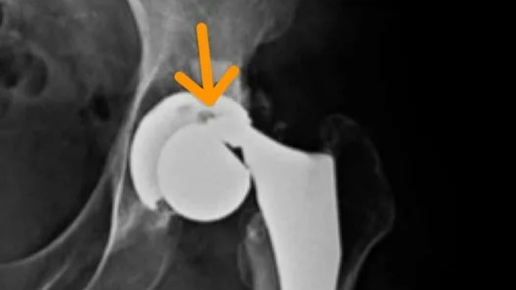

ЗАМЕНА СУСТАВА: ЧТО-ТО ПОШЛО НЕ ТАК